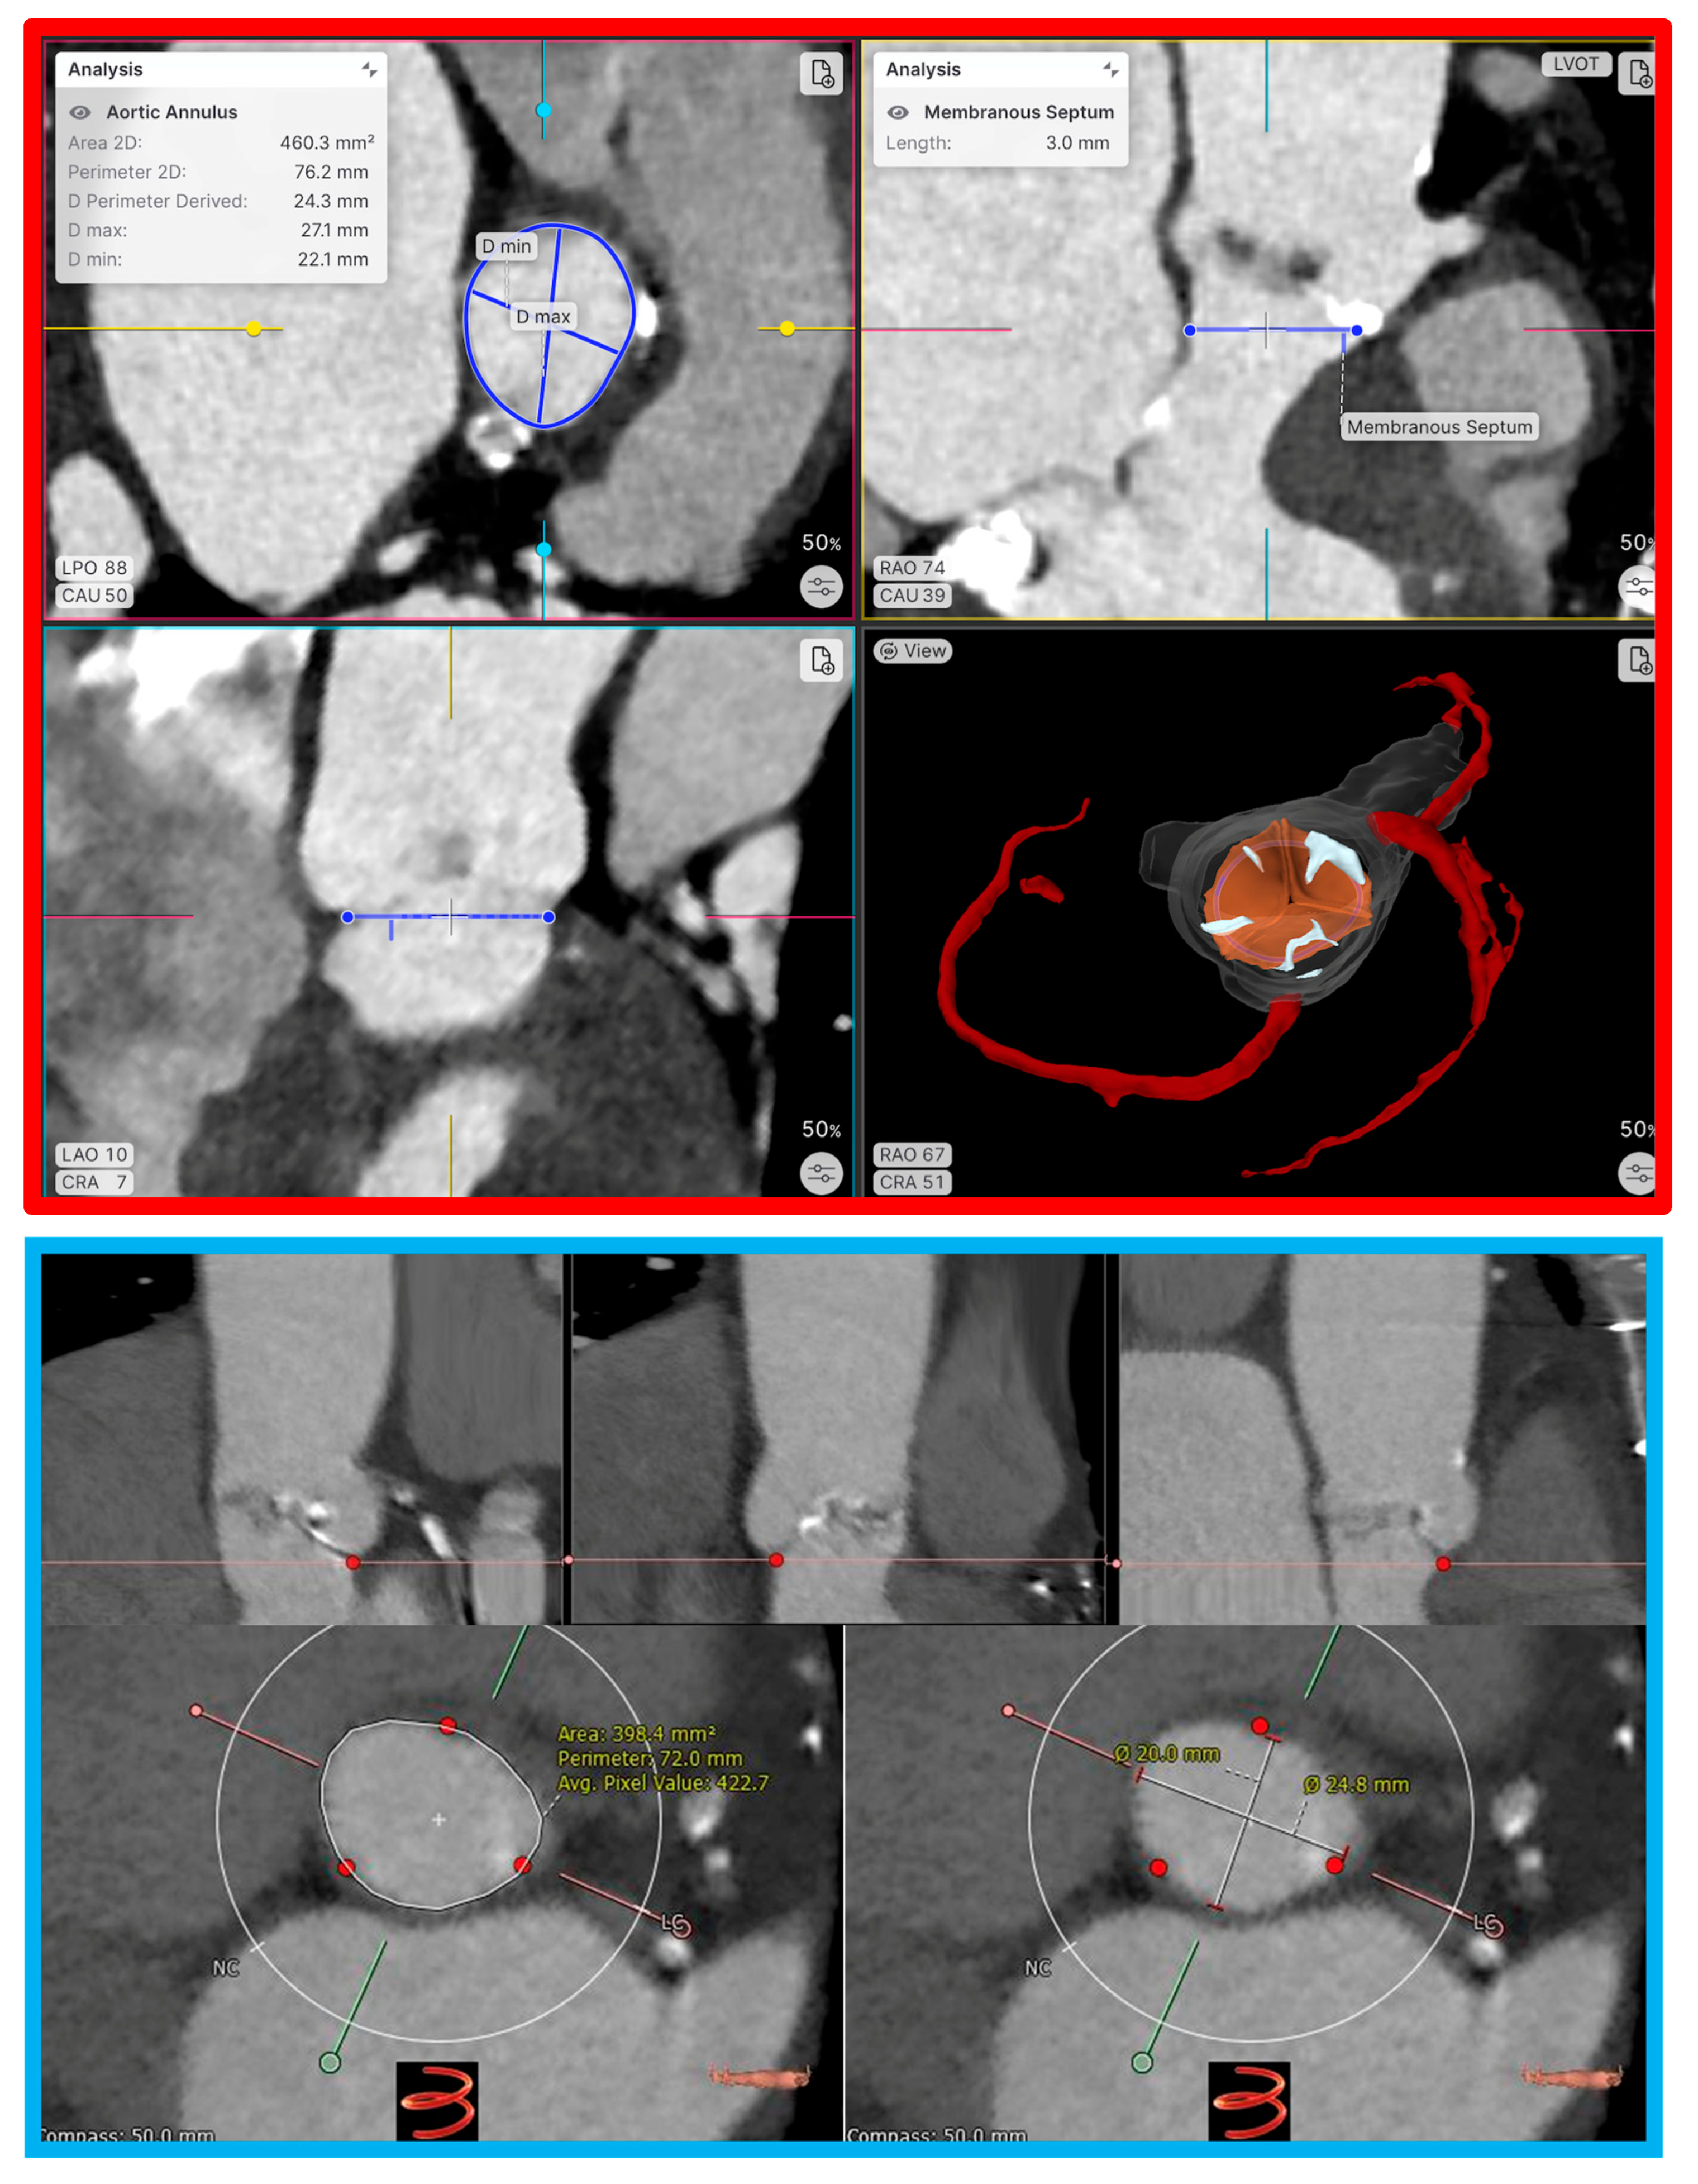

4.1. TAVI

4.1.1. Optimal Sizing

4.1.6. Prediction of Conduction Disturbances

4.3. Left Atrial Appendage Occlusion

4.3.1. Methods of Analysis for CT-Based Computational Modeling of LAAO